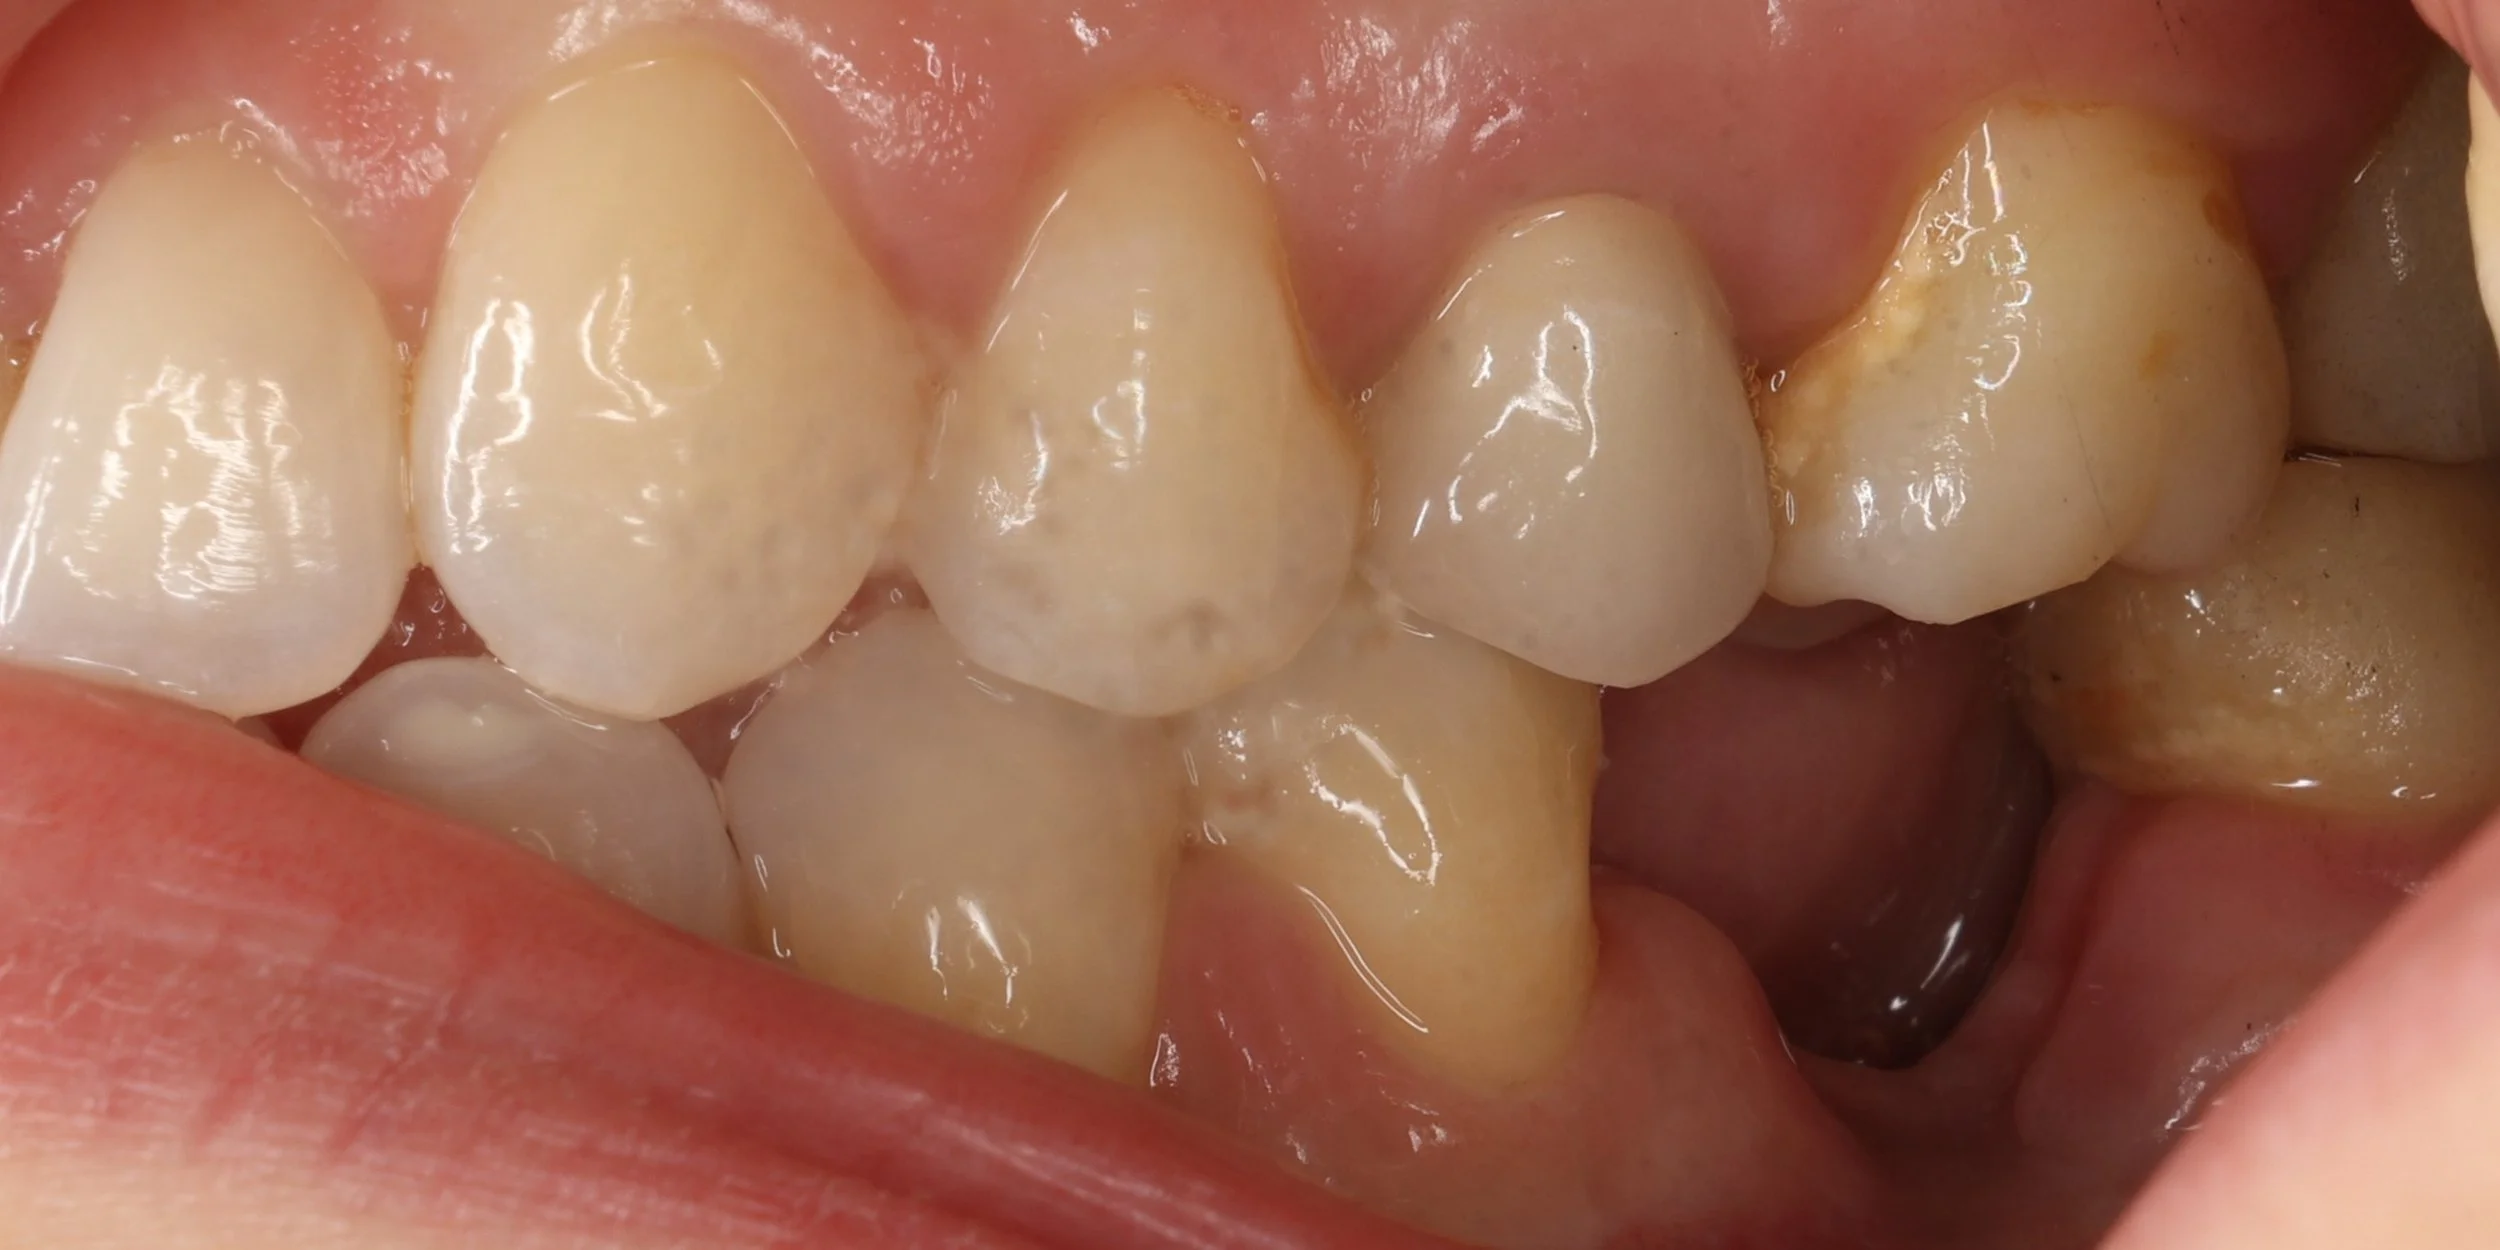

Relativement récents, les bridges collés cantilever postérieurs constituent une alternative fixe, fiable et véritablement minimalement invasive aux implants dans les secteurs postérieurs. Cette thérapeutique qui repose sur des indications bien précises est parfois débattue avec passion sur les réseaux sociaux ou dans les congrès scientifiques. Cependant des études cliniques existent, tout comme des recommandations validées dans des journaux internationaux. Leur succès repose sur des préparations et des principes biomécaniques rigoureux, pourtant simples à intégrer au quotidien. Cette intervention propose un guide clair et opérationnel incluant indications, étapes clés, protocoles d’adhésion et réglages occlusaux pour les mettre en œuvre avec confiance et reproductibilité.